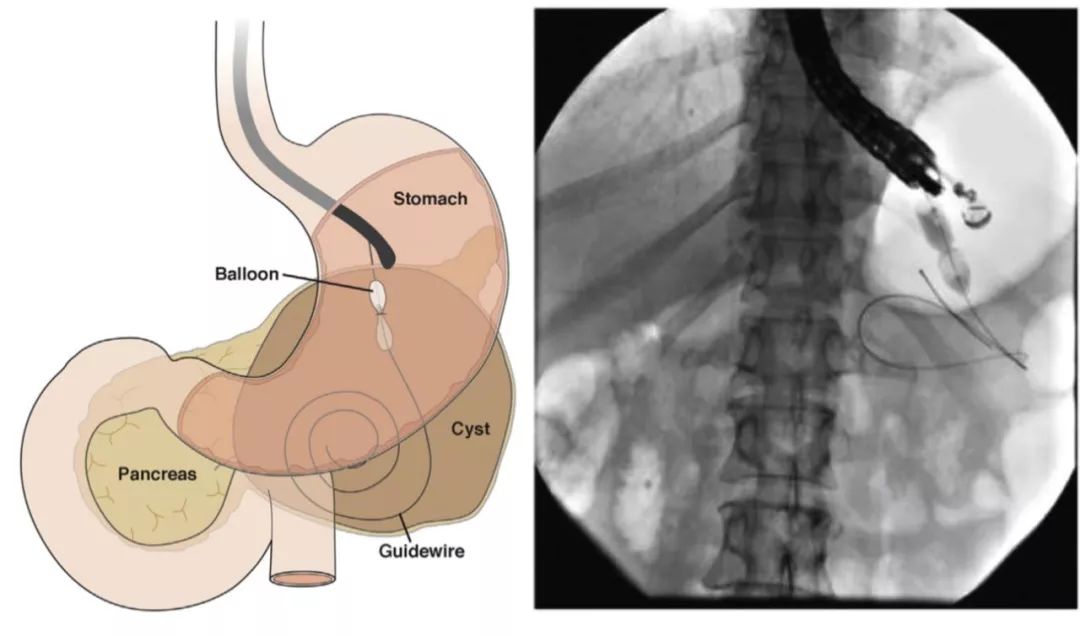

除了传统的手术方式,现在值得尝试的一种方式为经乳头放置胰管支架,使用支架对两个断端进行“桥接”(图6),另一种方式为跨壁引流,具体的做法是放置双猪尾支架,将囊液引流至胃肠道,但是支持这些做法的相关研究质量并不高。

权威研究说,胰腺液体积聚引流,内镜可以这样用

图6 经乳头放置胰管支架